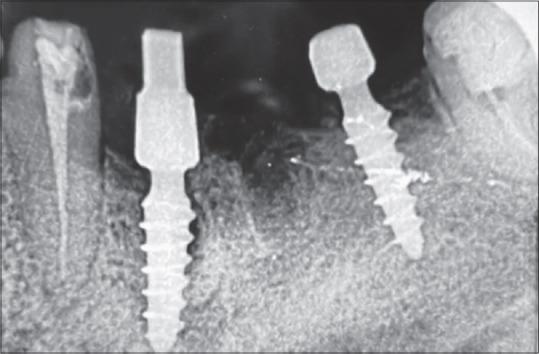

Comparative Analysis of Crestal Bone Levels of Basal Implants and Conventional Implants: A Clinico Radiological Study.

This study presents a comparative analysis of crestal bone levels, keratinized gingiva width (KGW), and gingival thickness (BGT) between basal and conventional dental implants over a 6-month period in the mandibular posterior region.

A total of 20 patients were divided into two groups: Group A (basal implants) and Group B (conventional implants). Both groups underwent flapless implant placements, with immediate loading for basal implants and delayed loading for conventional implants.

The results demonstrated significant differences in crestal bone levels, KGW, and BGT between the two groups. The basal implant group exhibited greater mean changes in crestal bone levels (0.35 mm), KGW (0.27 mm), and BGT (0.30 mm) compared to the conventional implant group. These findings suggest a potentially higher risk of bone loss and soft tissue alterations with basal implants, likely due to the biomechanical stresses associated with immediate loading.

The study concludes that while basal implants offer the advantage of immediate loading, they may also present challenges related to bone and soft tissue stability.